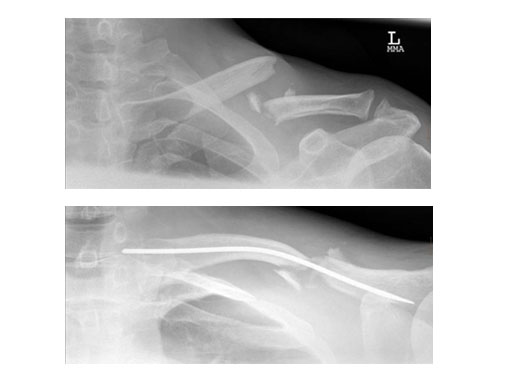

Cases provided by Vinzenz Smekal, Innsbruck, Austria

Case 2: 51 years, male, hit by tree